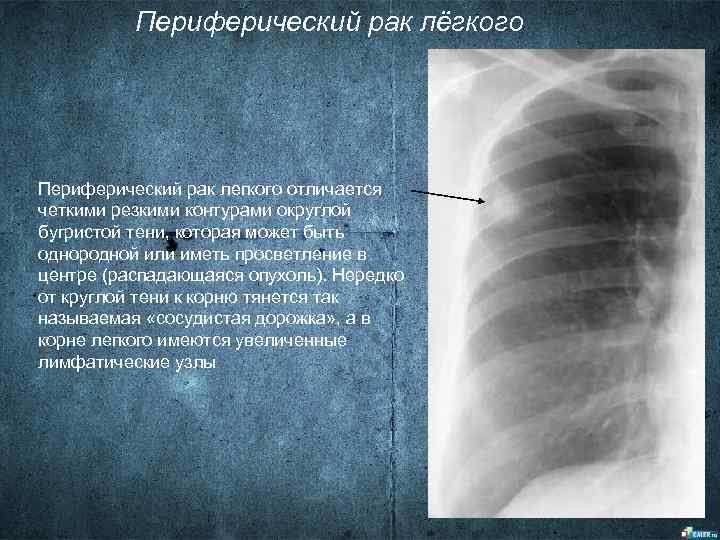

Раздел: Вселенная идей